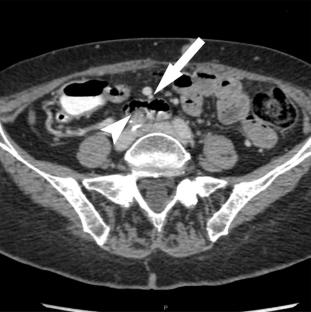

Our institutional review board approved this retrospective study. CT scans of 21 patients (11 women, 10 men) with surgically confirmed internal hernia and 52 control patients (23 women, 29 men) in whom internal hernia was suspected on CT but subsequently excluded surgically were reviewed. Six CT signs were evaluated: non-duodenal small bowel (ND-SB) behind the superior mesenteric artery (SMA), right-sided jejunojejunal anastomosis in applicable patients, “swirl” sign, superior mesenteric vein compression, “mushroom” sign, and clustered small bowel (SB) loops. Sensitivity, specificity, and odds ratios with 95% confidence intervals were calculated for each sign using logistic regression.

Logistic regression identified the “mushroom” sign, clustered SB, and ND-SB behind the SMA as significant independent predictors of internal hernia with an area under the receiver operating characteristic curve of 0.746. The sensitivity, specificity, and odds ratio of the “mushroom” sign, clustered SB, and ND-SB behind the SMA were 38.1%, 86.5%, 3.96 (95% CI, 1.21–12.97), 47.6%, 75.0%, 2.73 (95% CI, 0.94–7.89), and 33.3%, 88.2%, 3.75 (95% CI, 1.08–13.02), respectively.

The “mushroom” sign, clustered SB, and ND-SB behind the SMA are valuable CT findings in diagnosing internal hernias irrespective of Roux-en-Y anastomosis. In particular, ND-SB behind the SMA and the “mushroom” sign are highly specific.